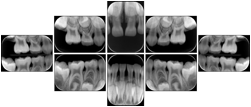

6 Standard + 4 Bitewing C Dental Image Layout

DL-P002E

Reference:

01

Standard

11, 12, 21, 22

11

32, 31, 41, 42

20

Bitewing

18, 17, 16, 15, 48, 47, 46, 45

21

17, 16, 15, 14 47, 46, 45, 44

23

27, 26, 25, 24, 37, 36, 35, 34

24

28, 27, 26, 25, 38, 37, 36, 35